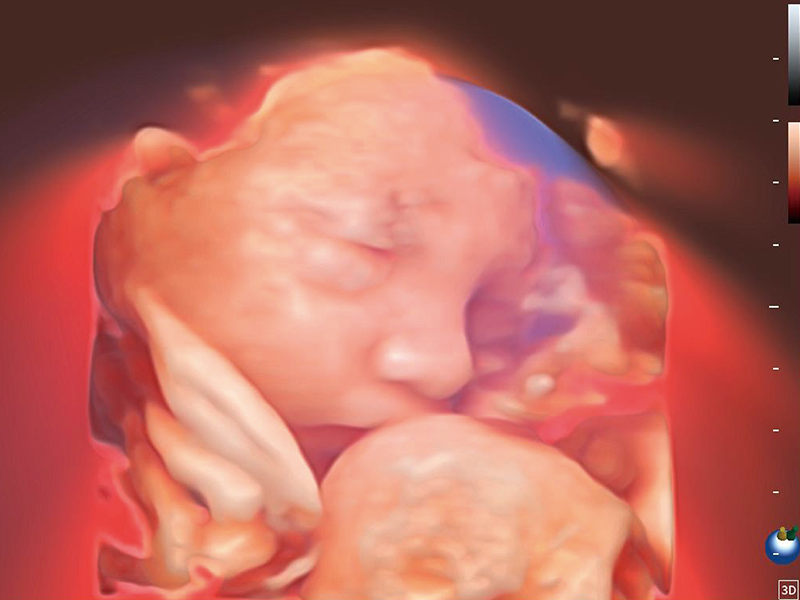

Image quality always lies at the core of definitive clinical outcomes. The P80 Elite introduces evolutional transducers with excellent 2D image clarity and color sensitivity for more confident assessment in anatomy and pathology.

S-Live Studio